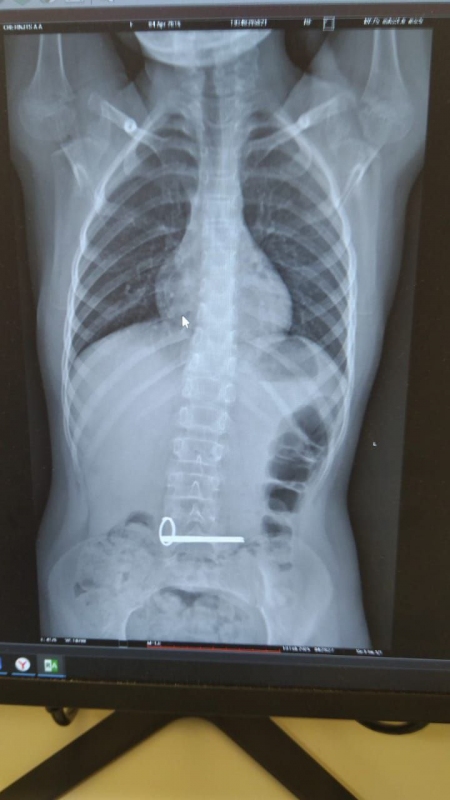

8-летний житель Оренбуржья ночью поступил в отделение экстренной помощи ОДКБ с инородным телом в желудке. Школьнику сделали снимок, на котором доктора увидели четкое изображение двух ключей, скрепленных кольцом. Эндоскопистам предстояло извлечь ключи, введя маленького пациента в наркоз. Связку достали без каких-либо осложнений для ребенка.